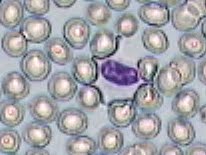

Práctica de Frotis sanguíneo 15